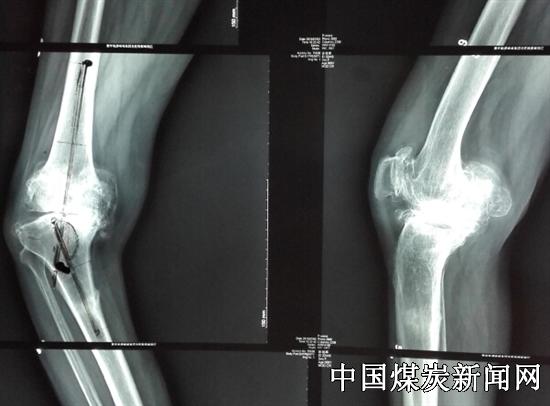

7月3日,就诊总医院邯郸院区的一名徐姓患者,右侧膝关节重度内翻畸形达43°,双膝关节疼痛10余年,伴脑出血后遗症,右下肢肌力减弱,左膝中度内翻畸形约20°患者行走困难,这使患者带背负极大心理压力,给她的日常生活带来极大不便。

该院骨三科主任医师韩守江从事关节置换手术近20年,手术2000多例,面对慕名而来的患者,他仔细询问病史,查看病情见患者右膝内翻严重达43°,右膝内侧胫骨平台缺损达4cm,病例极为罕见。通过研究病例,为患者制定出膝关节置换手术方案。为了准确手术,他们术前针对患者右膝详细制定截骨矫形方案,防止术中因截骨误差,导致下肢力线恢复不良,肌力弱易导致关节松弛。以为患者负责的态度,党员韩守江反复论证后,决定使用3D技术重建患者右膝关节骨性结构,通过“私人订制”定制符合个体的手术器械,施行个体化手术方案。

高科技3D打印关节技术的使用,可提前将患膝关节以实体模型方式展现出来,一方面可使主刀医生在患者身体未实施手术前,于体外进行模拟手术操作,反复、详细模拟操作,明确了术中截骨量大小及力线纠正方案;另一方面,通过3D模型同时为患者定制专用个体手术器械